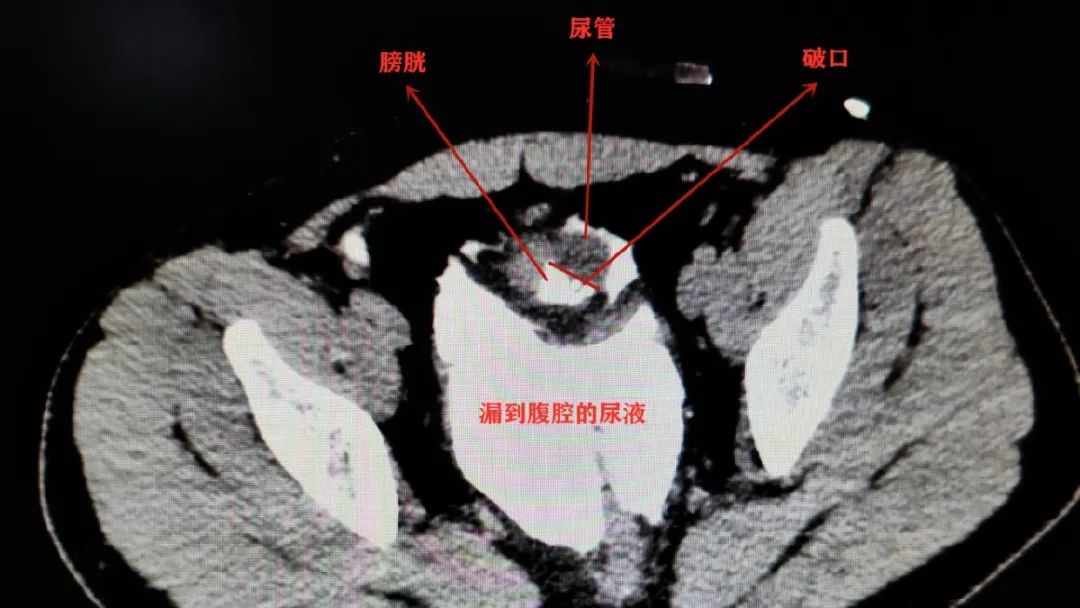

“如果再不及时手术,可能生命都会受到威胁。”成都市第三人民医院泌尿外科副主任医师袁仁斌博士告诉记者,当时,小李膀胱有一个4*3cm的破洞,尿管顺着洞“跑”到了腹腔内。因为尿液在腹腔内蓄积了很长时间,已经引发了比较严重的腹膜感染。

膀胱很容易外力撞破吗?袁仁斌说,尿量过多导致膀胱过度充盈,撞击的外力才会“有机会”对充盈的膀胱造成直接的作用,“如果能及时排尿,也许就不会引起这次伤害了。”